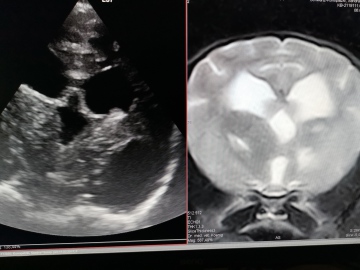

Wie man sieht, kann aber auch eine Ultraschalluntersuchung durch die noch geöffnete Fontanelle relativ detailliert die Gehirnventrikel darstellen.

Beide Scanbilder zeigen deutliche Vergrößerung (dunkle Flächen) der Seitenventrikel besonders des rechten. Der junge Hund zeigte Blindheit und ständiges Drehen insbesondere bei Aufregung.